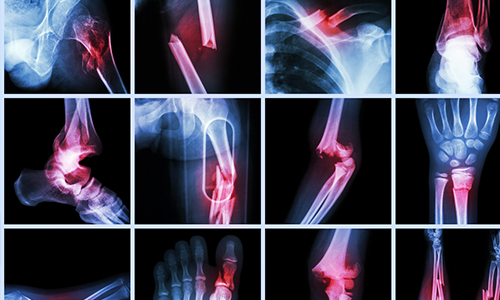

Knee or joint discomfort can hold you back from living fully. Our orthopedic experts are here to bring you long-term relief through accurate diagnosis and expert care. Consult Us Today and take the first step toward pain-free movement.